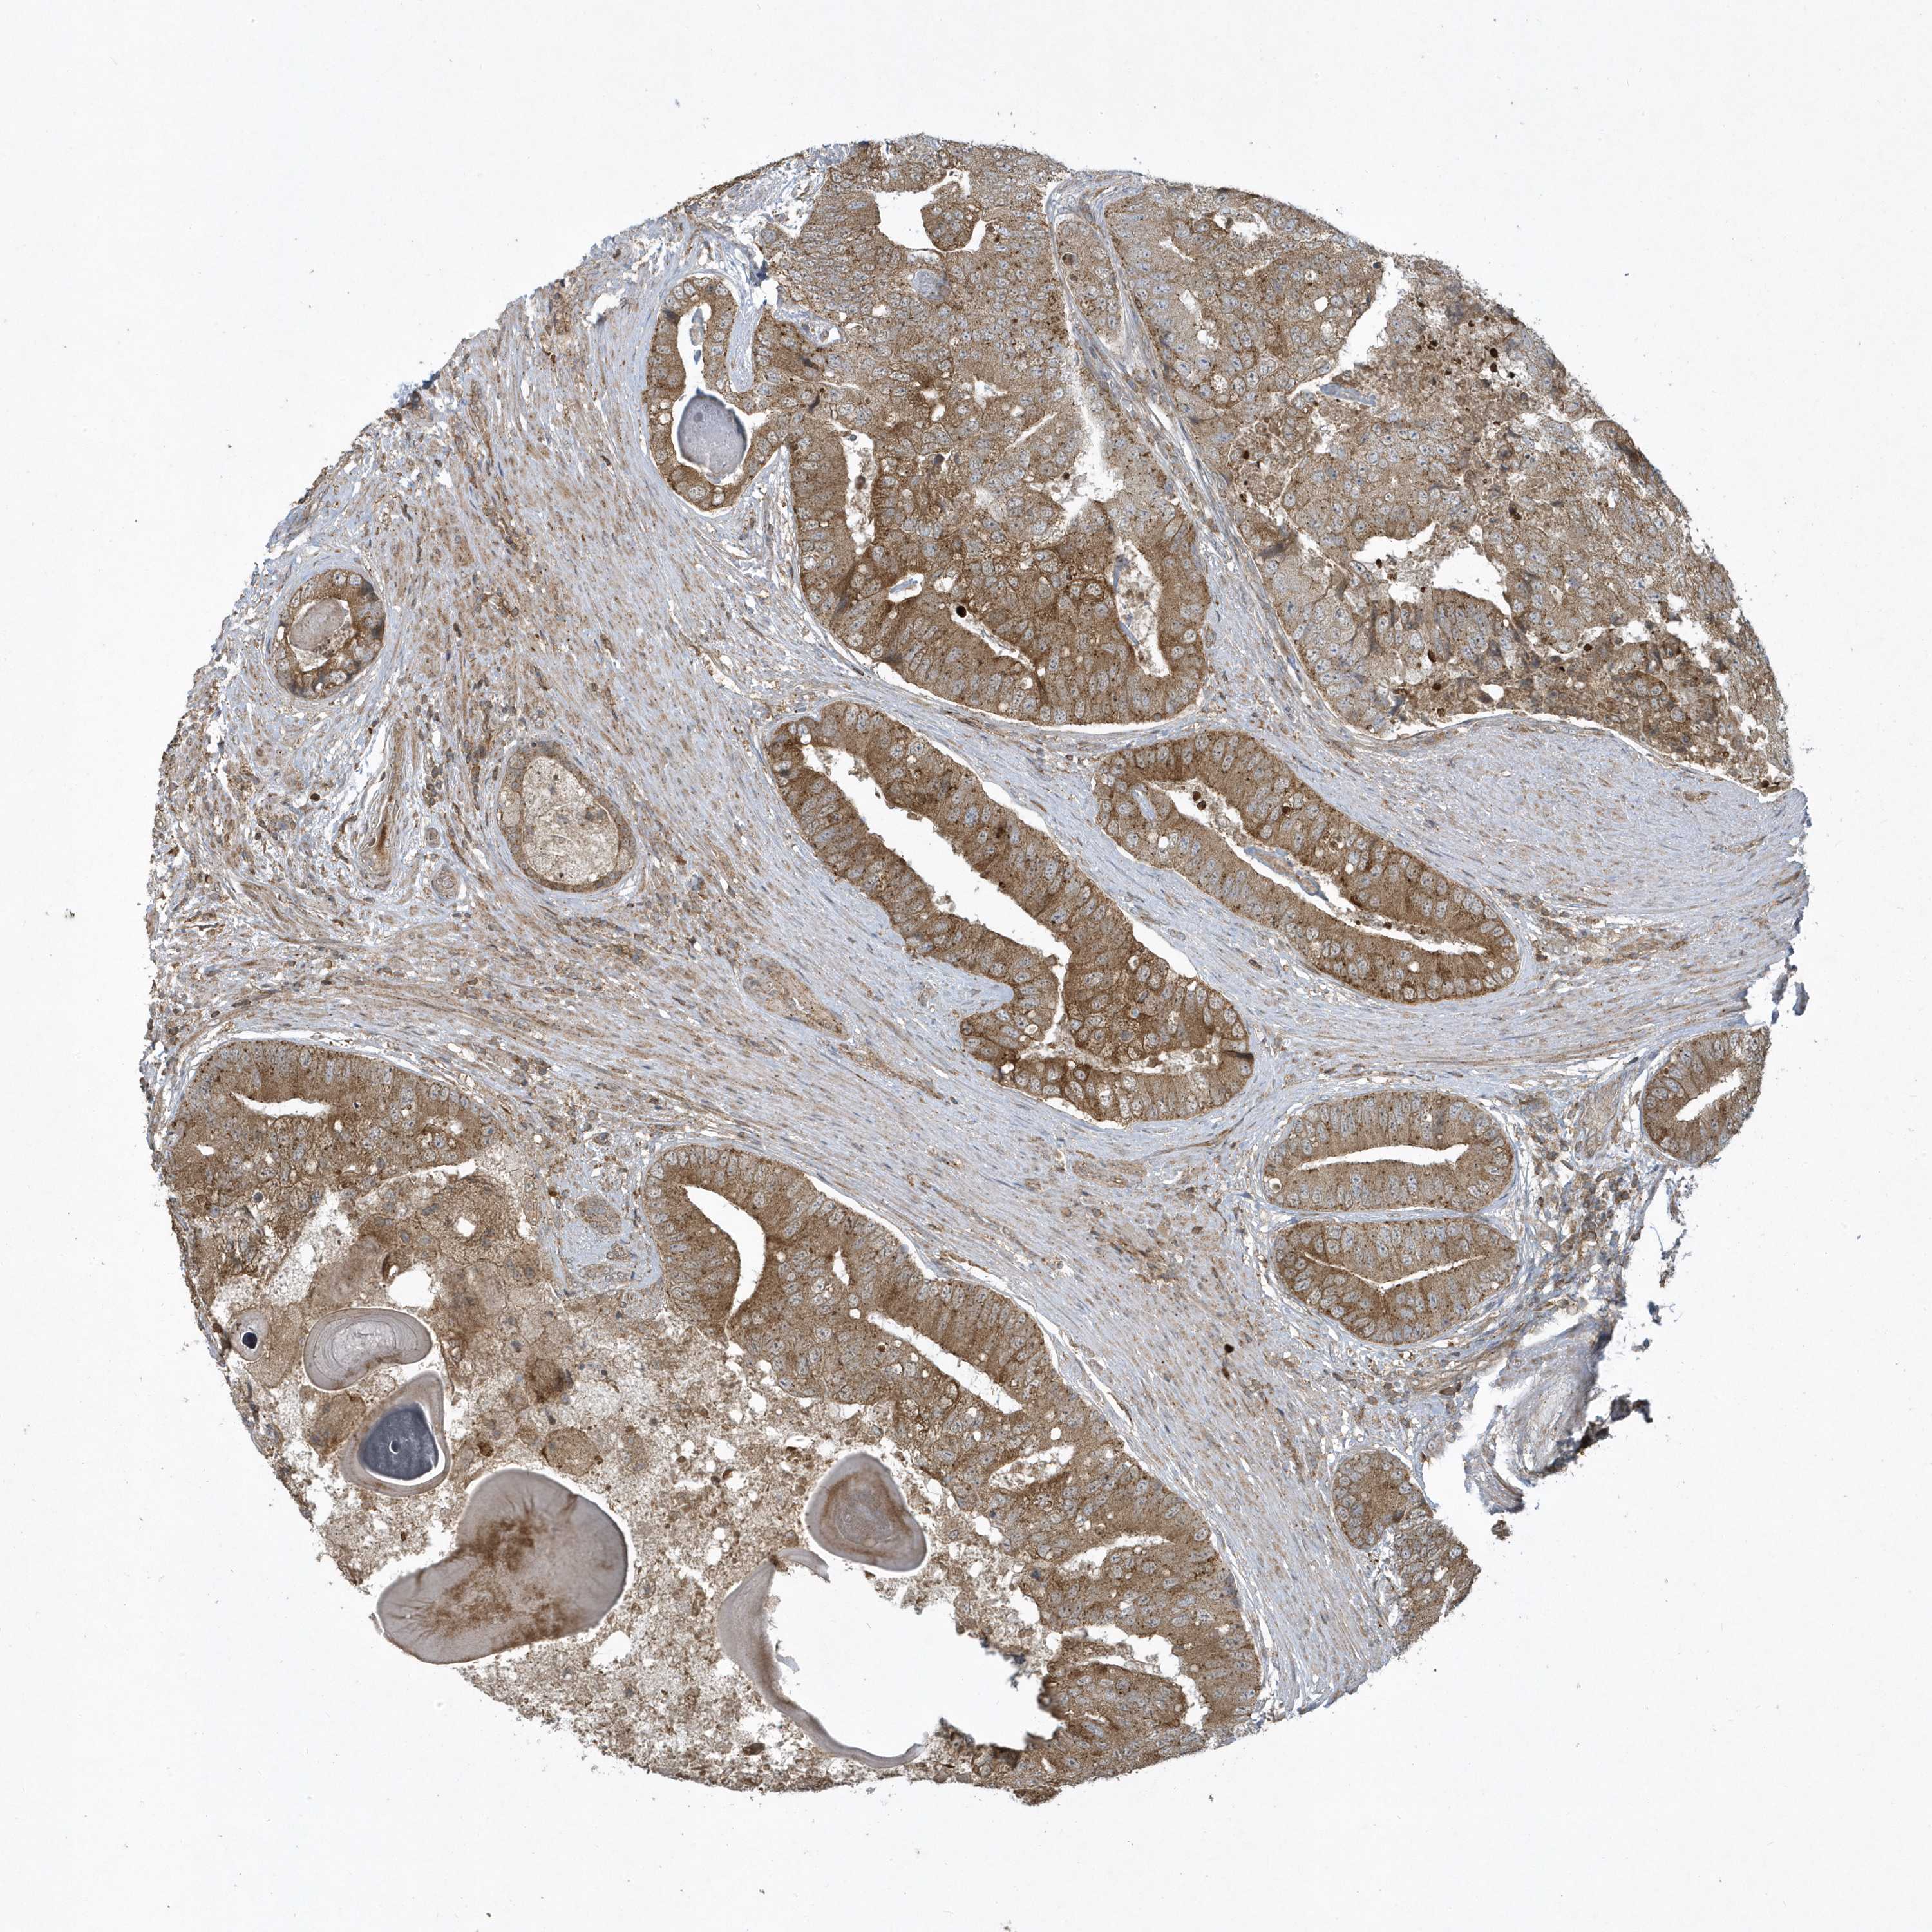

PROSTATE CANCER - Protein expressioni

A mouse-over function shows sample information and annotation data. Click on an image to view it in a full screen mode. Samples can be filtered based on level of antibody staining by selecting one or several of the following categories: high, medium, low and not detected. The assay and annotation is described here.

Note that samples used for immunohistochemistry by the Human Protein Atlas do not correspond to samples in the TCGA dataset.

Antibody stainingi

Antibody staining in the annotated cell types in the current human tissue is reported as not detected, low, medium, or high, based on conventional immunohistochemistry profiling in selected tissues. This score is based on the combination of the staining intensity and fraction of stained cells.

Each image is clickable and will lead to virtual microscopy that enables deeper exploration of all samples and also displays staining intensity scores, fraction scores and subcellular localization as well as patient and tissue information for each sample.

Antibody HPA035800

Staining

High

Medium

Low

Not detected

Intensity

Strong

Moderate

Weak

Negative

Quantity

>75%

75%-25%

<25%

None

Location

Nuclear

Cytoplasmic/membranous

Cytoplasmic/membranous,nuclear

Adenocarcinoma, High grade

Adenocarcinoma, Low grade